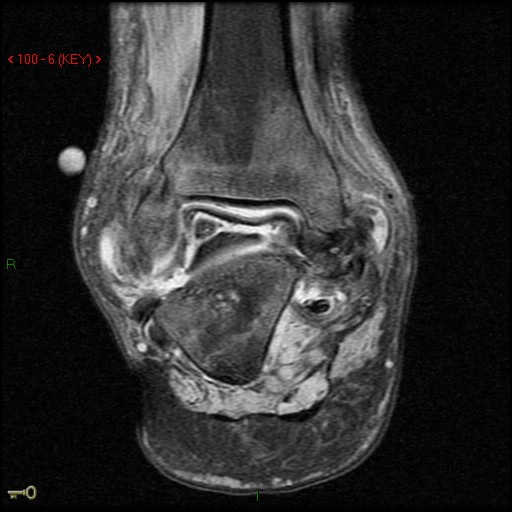

Figure 1 for case AVN talus

Figure 1

Discussion

Likely charcot variant & AVN with talar neck fracture.

AVN talus